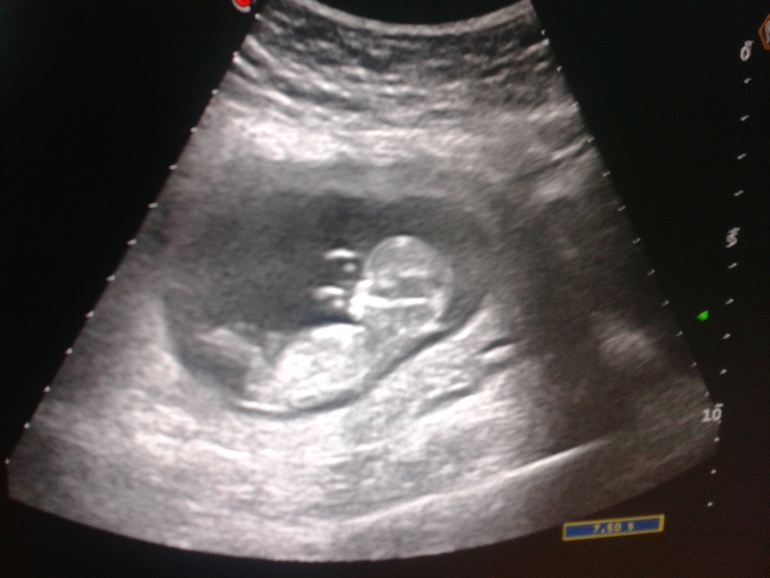

Пол малыша Девочки, смотрю тут многие смотрят пол по половому бугорку 12 недельного УЗИ. Вот я тоже нашла фотку, но вроде тут ничего не видно или я ничего не понимаю))))). Девочки как думаете? У кого глаз наметан?))))))

тут бугорка не видно ,видно ножку и пуповину мне кажется. Должна быть хотя бы такая видимость,чтоб определить...)

В 12 недель и самый опытный узист не возьмётся сказать. http://www.baby.ru/blogs/post/28474745-25801154